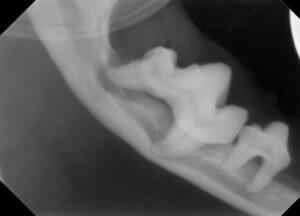

3.レントゲンでは、顎の骨が歯周病により骨折しやすい状態が確認されます。

4.下顎の顎先の骨も薄い状態です。

5.下顎の骨が溶けて、骨折しやすくなっています。